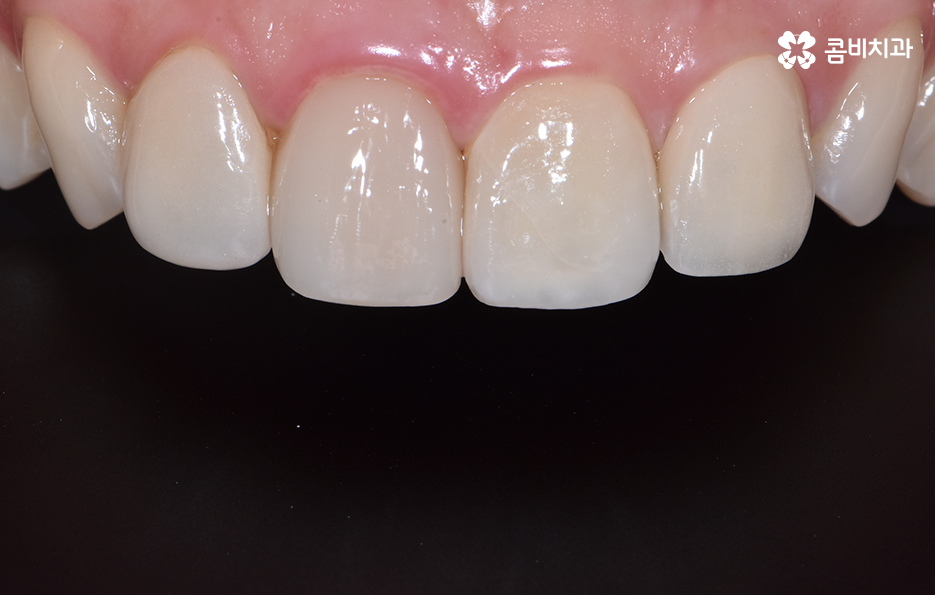

마지막으로 소개드릴 앞니 충치치료 방법은 라미네이트입니다.

충치가 앞니에 발생했을 때 초기에는 레진으로

치료를 하지만 손상이 좀 더 심한 경우 라미네이트를 활용합니다.

라미네이트는 충치 치료 방법보다는 빠른 치아성형 방법으로

많이 알려져 있는데 앞니의 벌어짐, 깨짐 등의 치료에도 많이 쓰입니다.

심미성이 우수하지만 치아의 겉면에 세라믹 박편을

붙이는 방식의 치료 방법이기 때문에

자연치아에 비해 내구성이 약한 편이므로

음식물을 섭취할 때 주의를 하시는 것이 필요합니다.